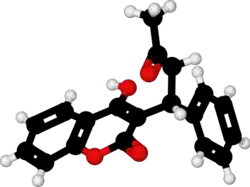

Chemistry

X-ray crystallographic studies of warfarin show that it exists in tautomeric form, as the cyclic hemiketal, which is formed from the 4-hydroxycoumarin and the ketone in the 3-position substituent.[79] However, the existence of many 4-hydroxycoumadin anticoagulants (for example phenprocoumon) that possess no ketone group in the 3-substituent to form such a structure, suggests that the hemiketal must tautomerise to the 4-hydroxy form in order for warfarin to be active.[80]